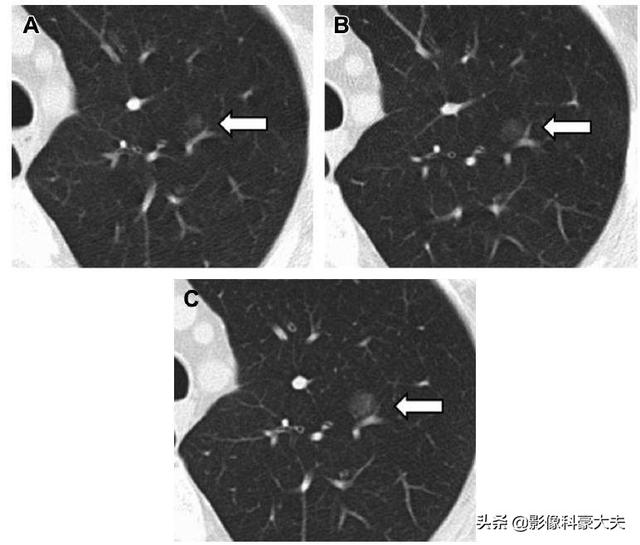

この文献は、6年前から成長し、進行性に増大したground glass noduleの症例であり、外科的病理結果はin situ腺癌であった。

一般に、高度な診断機器と技術を必要とする、非常に小さな顕微鏡的肺癌の場合は、次のような方法が必要である。洗練された建設後の詳細観察低線量スパイラルCTではこのような精度は得られない。